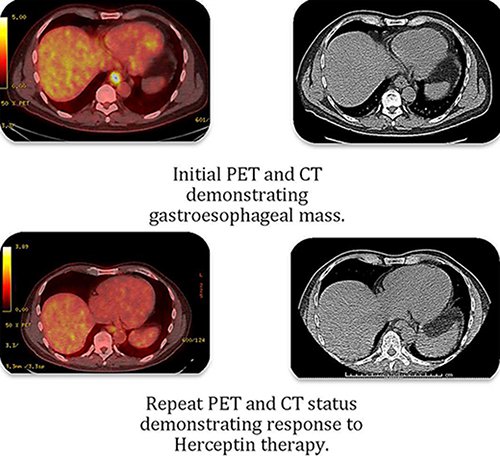

病例1:男,66岁,因胃食管返流与腹部不适被诊断为胃食管结腺癌。2014年2月,内镜检查发现4cm肿块,活检确认为T3N1Mx(图1-上),并于2014年3月接受了卡铂和紫杉杉的联合化疗,4月完成治疗。6月食管切除。然而,在3个月后复查发现右下肺结节,活检证明是转移性腺癌。ECOG评分为1,进行6次的奥沙利铂+亚叶酸钙+5-氟尿嘧啶联合化疗。组织标本检测发现过度表达HER2,因此,2015年1月,化疗方案加入曲妥珠单抗。6月PET CT完全应答后,仅曲妥珠单抗维持治疗(每3周6mg/kg),11月CT结果没有进展。2016年2月PET CT显示无复发、无进展。接受曲妥珠单抗治疗,多次ECHO监测心脏状态良好。最初诊断转移性腺癌至今3年多的时间,疾病依旧无复发、无进展(图1-下)。

图1